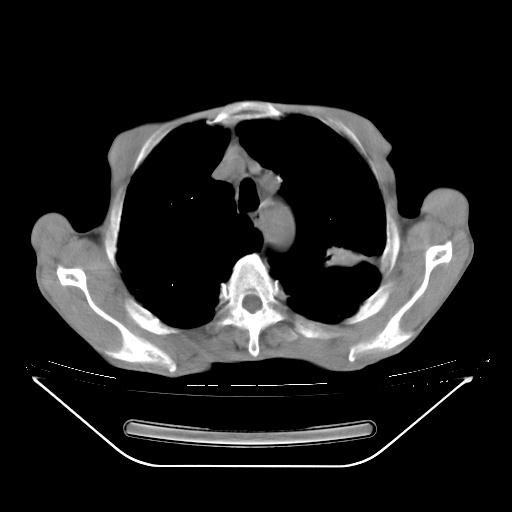

以下是引用随光逐影在2008-8-25 22:03:00的发言:[br]1)考虑右肺下叶周围性肺癌并肺内转移,腰椎附件转移。2)左上肺结核(结核球形成)。3)双肺肺气肿(多发肺大泡形成)。4)双肺门区及纵隔内多发淋巴结钙化。